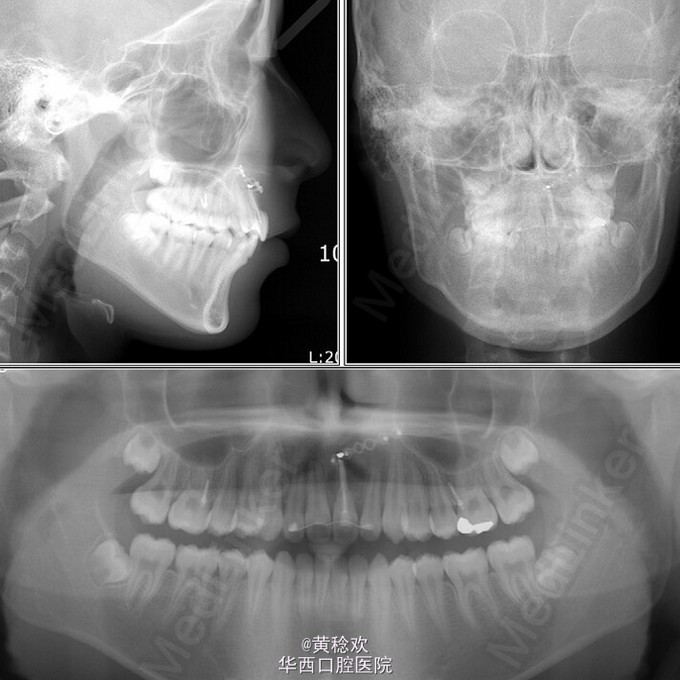

牙齿脱位对牙周膜、牙槽骨、牙龈、牙髓和牙骨质造成严重损害。脱位牙再植后经常伴有牙骨粘连等并发症。牙骨粘连指的是局部牙骨质和周围牙槽骨融合,多起因为牙齿正在萌出过程中或萌出后受到机械性、温度或者代谢产物刺激,对牙周膜造成损伤,好发于恒切牙。 牙骨粘连可通过临床和放射片检查诊断。临床检查包括低咬合状态、叩诊和松动度测试,最明显的特征是即便该牙施加正畸牵引力后也无法移动。整个牙的牙骨粘连可以通过放射片显示,其特征为无明显的牙周膜影响。但是如果该牙只有颊侧或者舌侧粘连,放射片上很难判断。近年来,CBCT的引入,可以逐渐将放射检查视野拓宽到3D层面,增强了对骨牙粘连的准确性。治疗骨牙粘连的方案包括:拔除、截冠、修复、手术半脱位、骨切开术和牵张成骨术等。